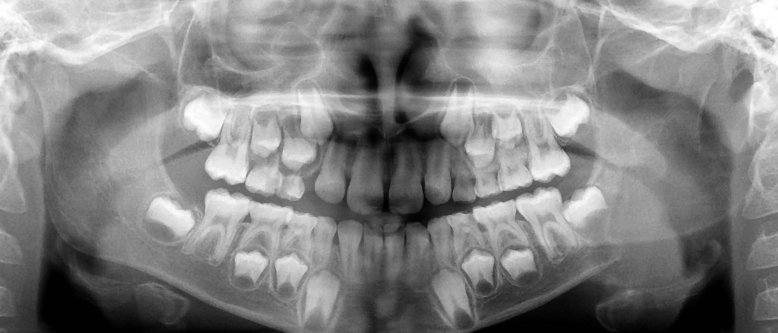

• Εντοπίζεται στην κάτω γνάθο και κυρίως στην οπίσθια περιοχή του σώματος και στην γωνία. Σπανιότερα μπορεί να εντοπιστεί στην πρόσθια περιοχή αυτής.

• Η αρχόμενη βλάβη απεικονίζεται σαν μονόχωρη διαύγαση ενώ αργότερα μετατρέπεται σε πολύχωρη με τη μορφή φυσσαλίδων από σαπούνι ή κερύθρας.

• Συνήθως έχει σαφή και καλά καθορισμένα όρια.

• Η αλλοίωση μπορεί να λάβει μεγάλες διαστάσεις, να προκαλέσει διόγκωση, λέπτυνση και διάτρηση των συμπαγών πετάλλων καθώς και μετατόπιση των γειτονικών δοντιών. Η απορρόφηση των ριζών είναι σπάνια.